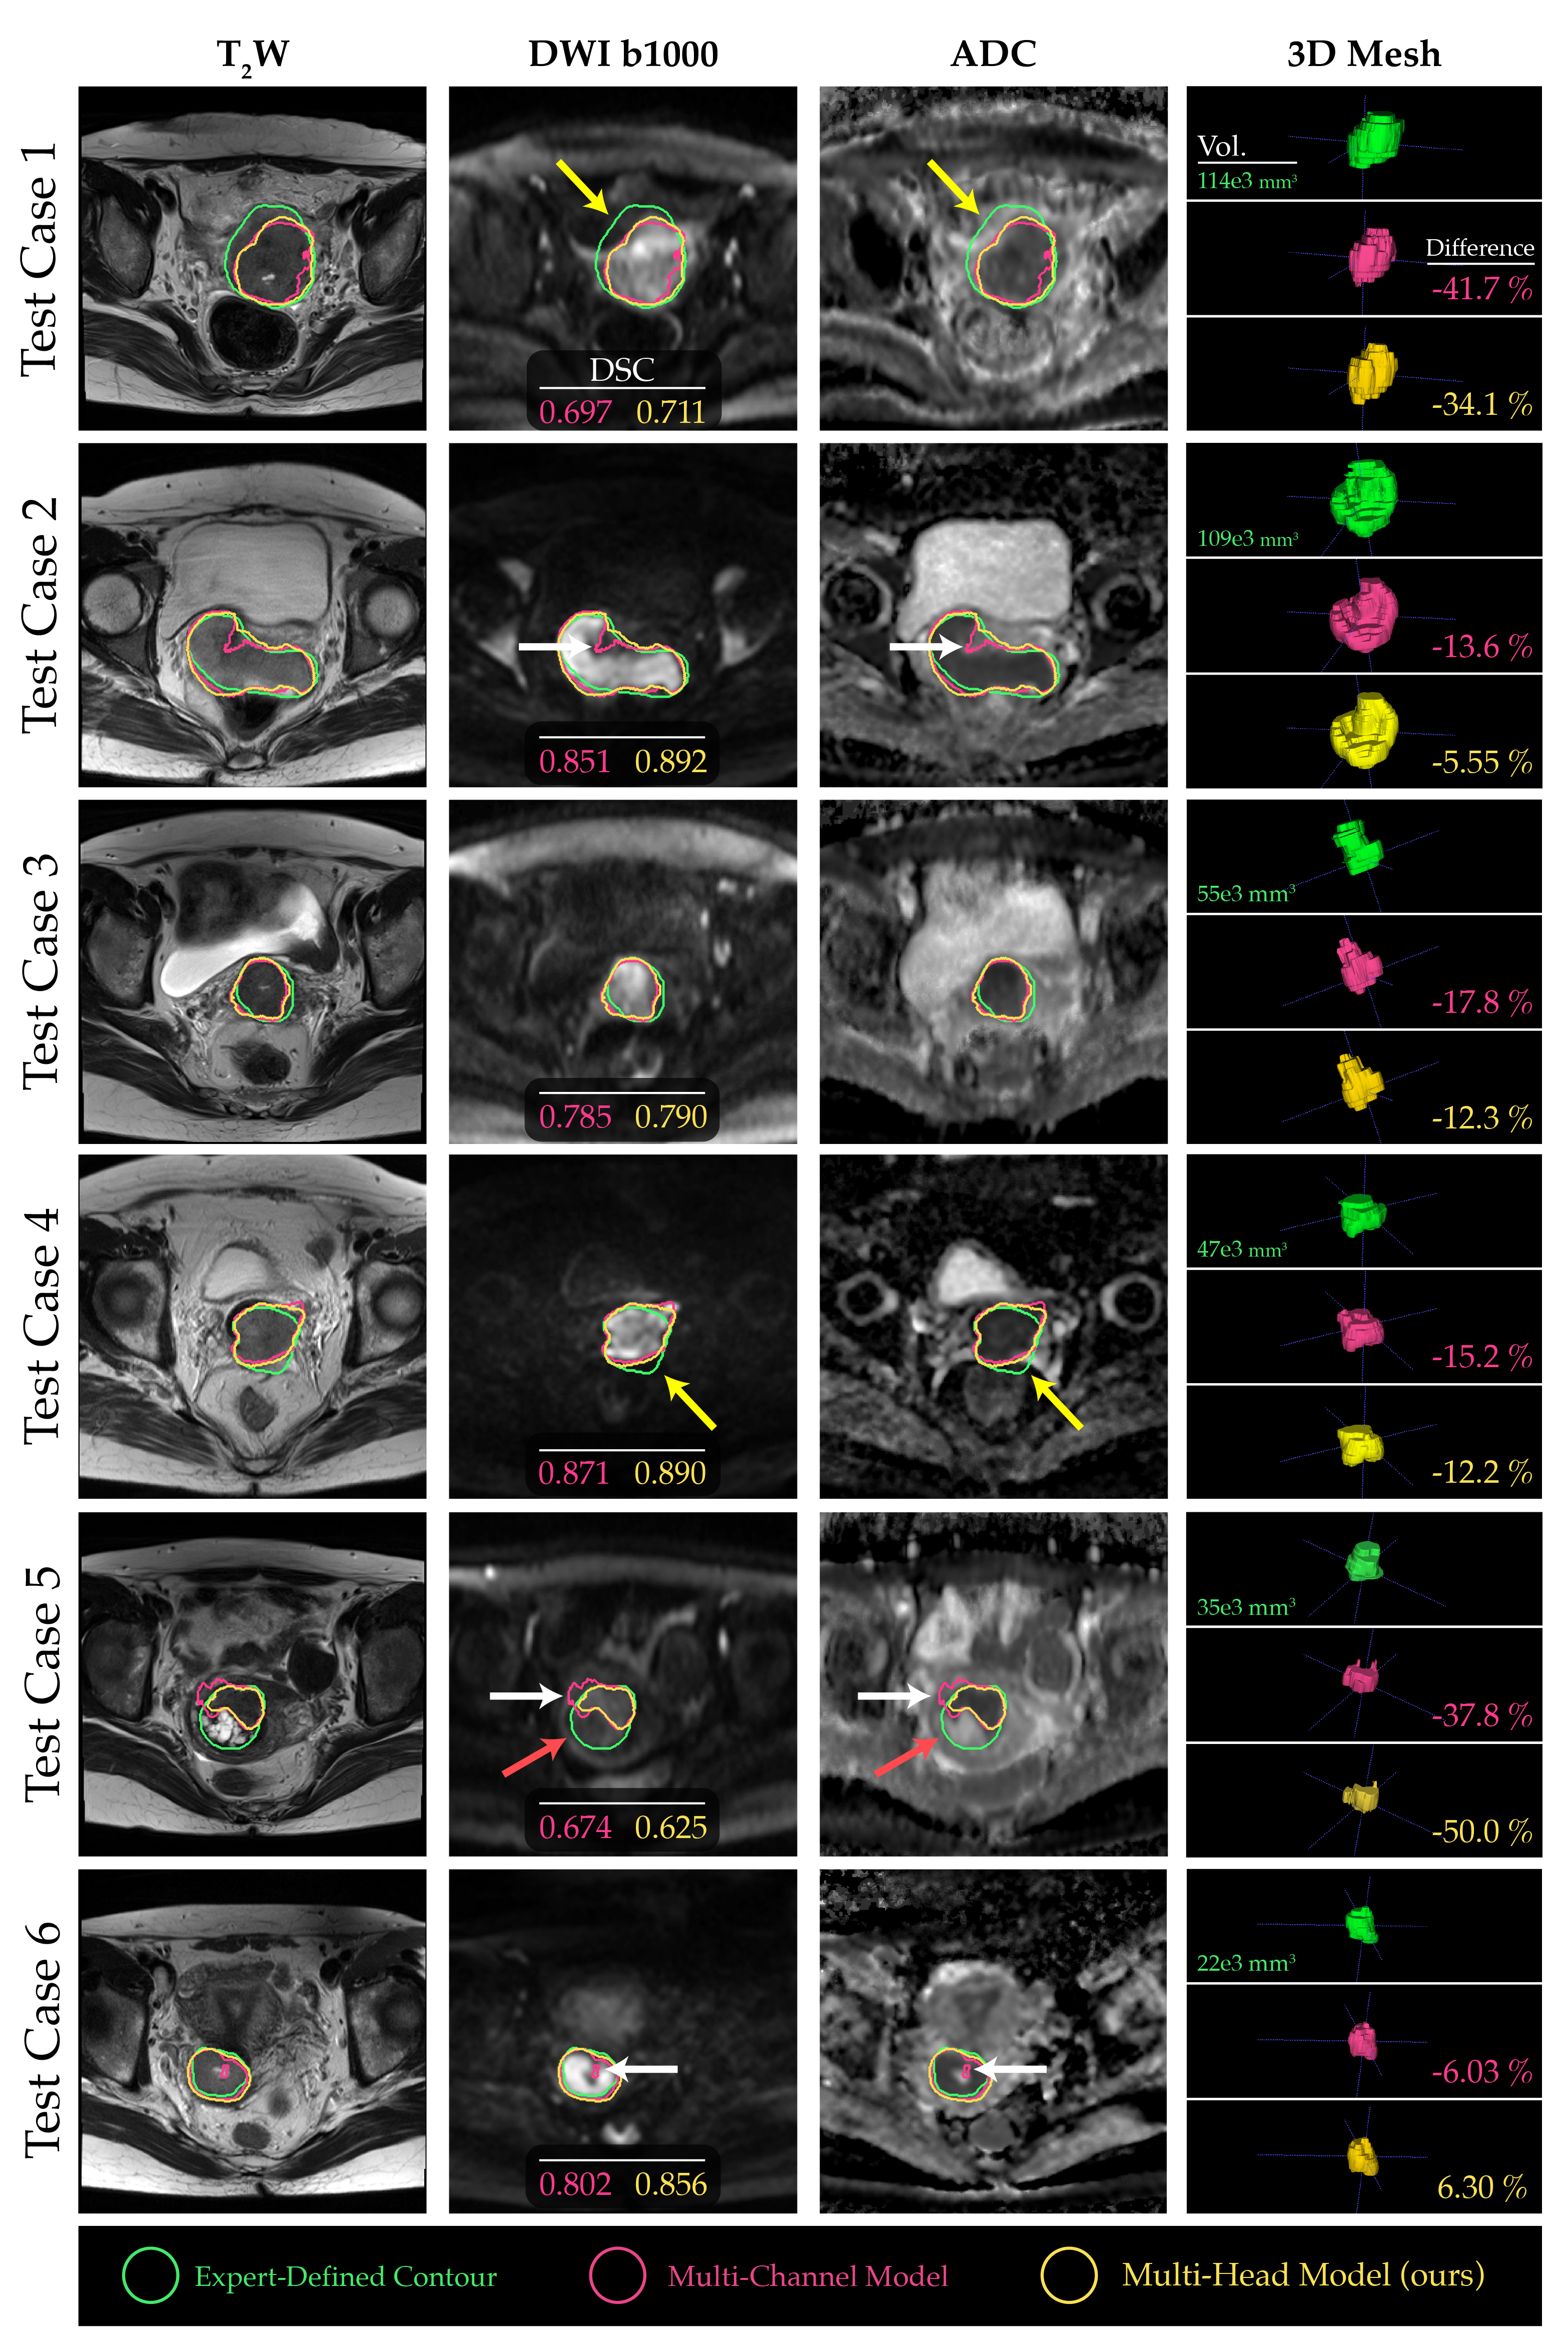

The comparison of segmentations obtained from the baseline multi-channel and the proposed multi-head models revealed that multi-head model 3 exhibited superior performance across the quantitative metrics analyzed (Figure 3a-d). Specifically, the median DSC values for the multi-channel model, multi-head model 1, multi-head model 2, and multi-head model 3 were 0.788 (confidence interval (CI), 0.568–0.776), 0.805 (CI, 0.538-0.769), 0.796 (CI, 0.537-0.776), and 0.823 (CI, 0.595-0.797), respectively (Figure 3a). However, the performance differences between the proposed multi-head models were not significantly different compared with the multi-channel model (p>0.05). On average, all models underestimated tumor volume compared with the contours drawn by the clinician, with the median relative percentage volume differences for each model of -14.4%, -18.9%, -9.7%, and -12.0%, respectively (Figure 3d). The multi-head model 3 demonstrated the best quantitative scores compared to the other experimental architectures, therefore, the segmentation contours predicted by this model were compared with those obtained from the baseline multi-channel model (Figure 4).

Refer to caption

Figure 4: Comparative evaluation of the baseline multi-channel and proposed multi-head models for 6 test cases, arranged in descending order of tumor size. The yellow arrows indicate regions where distortion in DWI and subjectivity in tumor location make contour propagation from T2W images challenging. Conversely, the white arrows highlight regions where the proposed model performed better by capturing boundaries and contextual information compared to the baseline multi-channel model. The red arrows highlight tumor regions within the ground truth contours that do not exhibit strong impeded diffusion, thus remaining undetected by the DL models.